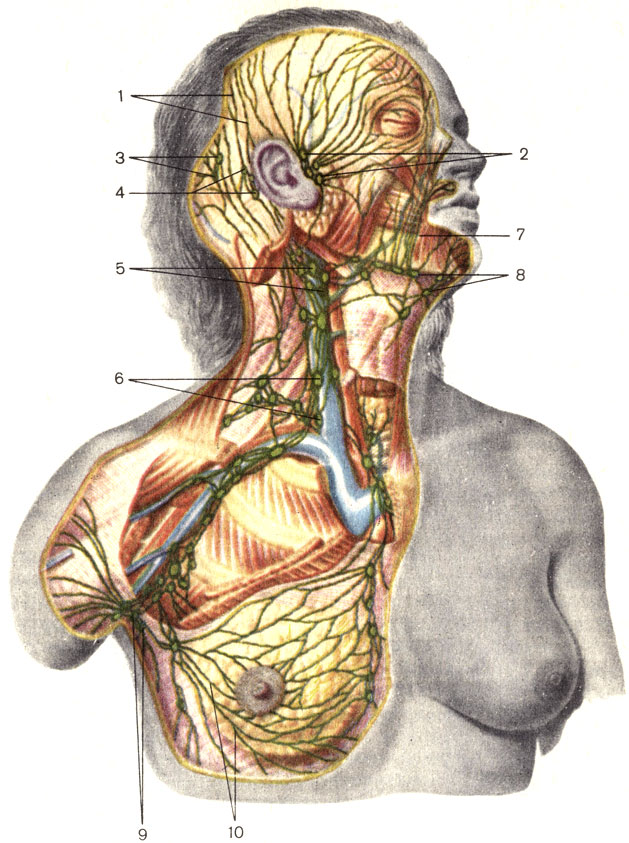

Изображения и схемы: как выглядит лимфа